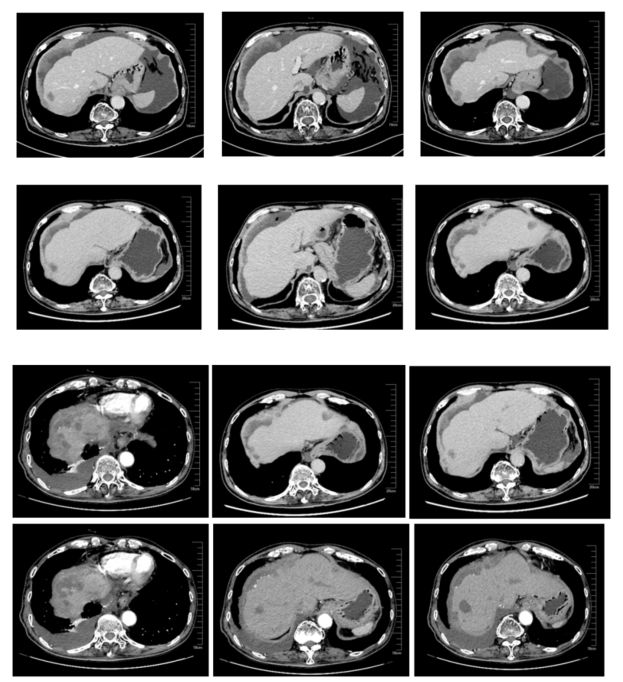

影像学评估:

图6、呋喹替尼单药治疗期间,影像学评估持续SD:第1排(2020-05)、第2排(2020-07)、第3排(2020-09)、第4排(2020-11)

影像学评估:腹膜及腹壁多发转移瘤,肝周假性黏液瘤形成,肝脏受侵,大致同前;肝脏多发转移瘤,较前变化不大。

图7、呋喹替尼联合用药期间,复查CT(2021-08-24),疾病稳定

2021-11-29 CT提示肺部转移,肝脏转移灶较前缓慢进展,CEA 1939.00 ng/mL,疗效评价PD。

图8、呋喹替尼联合用药期间,复查CT(2021-11-29),疾病进展